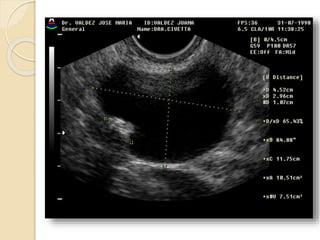

Ovarios

Los ovarios son órganos elipsoides

localizados en la fosita ovárica

situada en la pared pélvica externa.

Limitan con la fosa ovárica el

uréter y la arteria ilíaca interna

por detrás y la vena iliaca externa

por arriba.